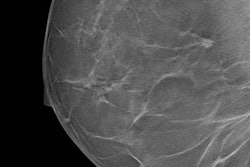

Breast density measurements calculated on full-field digital mammography (FFDM) and digital breast tomosynthesis (DBT) are comparable -- and so are median radiation dose values for dense breasts, according to Spanish investigators.

The findings are further evidence that radiologists can trust DBT for screening patients with dense breast tissue, wrote a team led by Dr. Maria Castillo-Garcia of the Complutense University of Madrid.

"Breast density measurements from both [digital mammography and DBT] lead to equivalent BI-RADS classification ... hence showing no difference in clinical outcomes," wrote the group, adding that "the median mean glandular dose values for dense breasts ... are similar for both FFDM and DBT imaging modalities" (Academic Radiology, July 2017, Vol. 24:7, pp. 802-810).

DBT has been shown to find more cancers and reduce recall rates when compared with digital mammography, whether or not a woman has dense tissue, according to the authors. But there has been concern that adding DBT to FFDM increases the radiation dose, a problem that can be exacerbated by dense tissue. To address that issue, some vendors have developed software that synthesizes 2D images from DBT exams, thus reducing the amount of radiation to which women are exposed.

Castillo-Garcia's group sought to compare breast density estimates from two measurement tools on FFDM and DBT and also analyze the impact of individual women's breast density values on mean glandular dose for both modalities. The team included 561 combination FFDM and DBT mammograms taken between November 2015 and January 2016 using Hologic's Selenia Dimensions system with C-View software, which generates synthesized 2D images.

Of the 561 exams, 227 were for women younger than age 50, and 334 were for women age 50 or older. Volumetric breast density was automatically calculated on each modality using Hologic's Quantra 2D and Quantra 3D software. The researchers also analyzed the impact of breast density values on mean glandular radiation dose for both FFDM and DBT.

They found that 71% of breasts imaged were classified under the same category for both modalities, with approximately half in BI-RADS density category C (heterogeneously dense) on both FFDM and DBT density calculations. When compared with the density algorithm for 2D images, DBT had a lower number of breasts in BI-RADS category D (extremely dense), at 43%, and a higher number of breasts in BI-RADS category A (entirely fatty), at 153%, the group found.

As for mean glandular dose, Castillo-Garcia and colleagues found a small increase of 5% or less on DBT in women with extremely dense breasts, but no statistically significant differences between breast density measurements from either of the Quantra algorithms and mean glandular dose.

The study shows that DBT is trustworthy in the screening context, the researchers concluded. In fact, it can replace FFDM -- overcoming that technology's limitations with dense breast tissue.

"According to our results, the small increase of mean glandular dose for women with extremely dense breasts supports the replacement of FFDM by DBT," the group wrote. "The availability of reconstructed 2D mammography from DBT acquisitions facilitates the replacement."